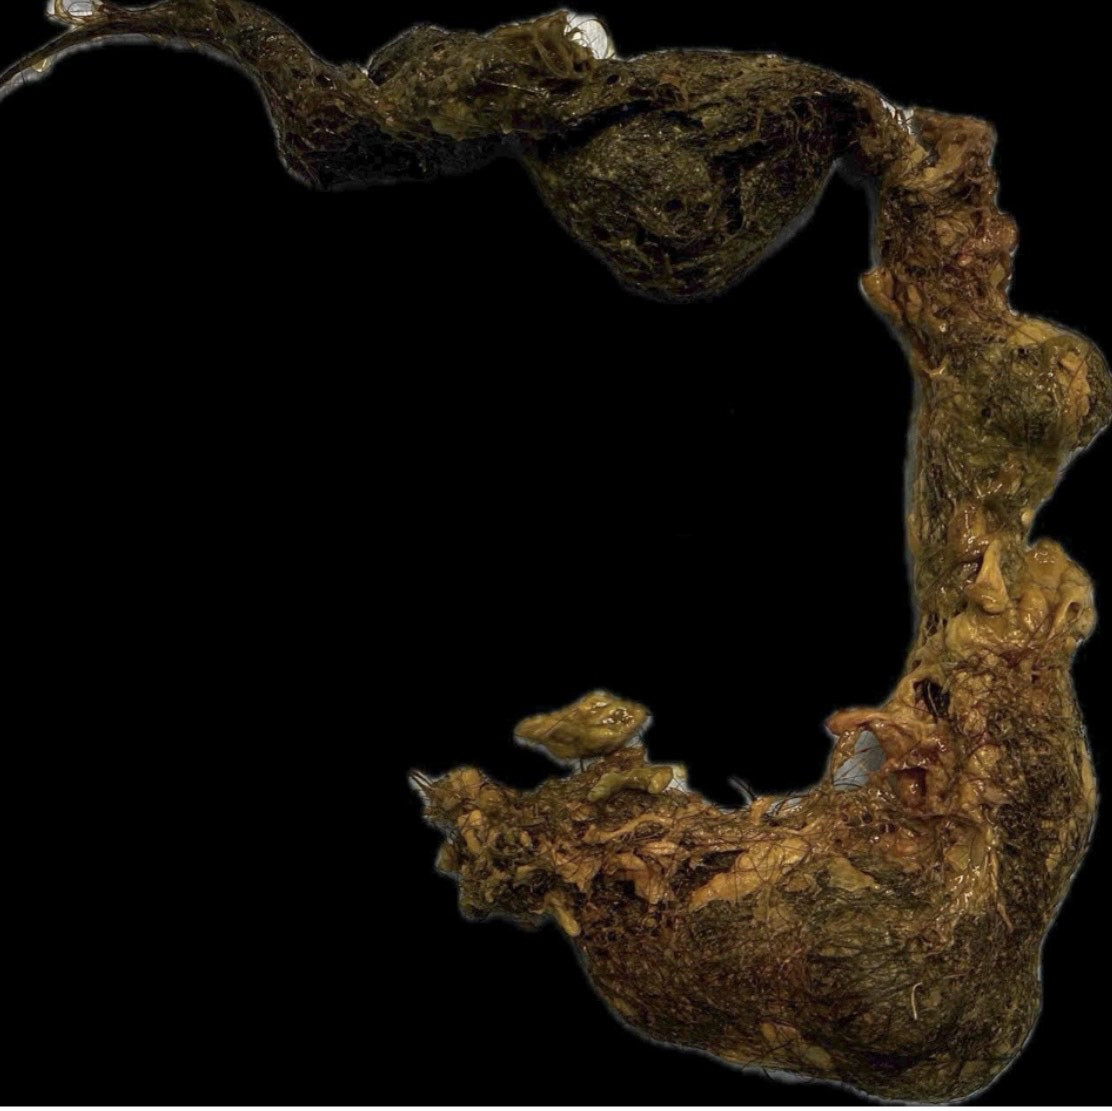

Khối tóc to và dày đóng thành khuôn cứng trong bụng gây tắc ruột bệnh nhi 9 tuổi. Ảnh:FV

Các bác sĩ FV đánh giá đây là ca bệnh hiếm gặp và phức tạp do búi tóc lớn, cuộn chặt và kéo dài qua nhiều đoạn ruột. Nếu xử lý không đúng cách, nguy cơ hoại tử và đe dọa tính mạng bệnh nhi cao.

Sự phối hợp nhịp nhàng giữa hai ê-kíp giúp hạn chế tối đa nguy cơ tổn thương ruột. Sau khoảng 3 giờ, búi tóc được lấy ra an toàn, giải quyết hoàn toàn tình trạng tắc ruột.